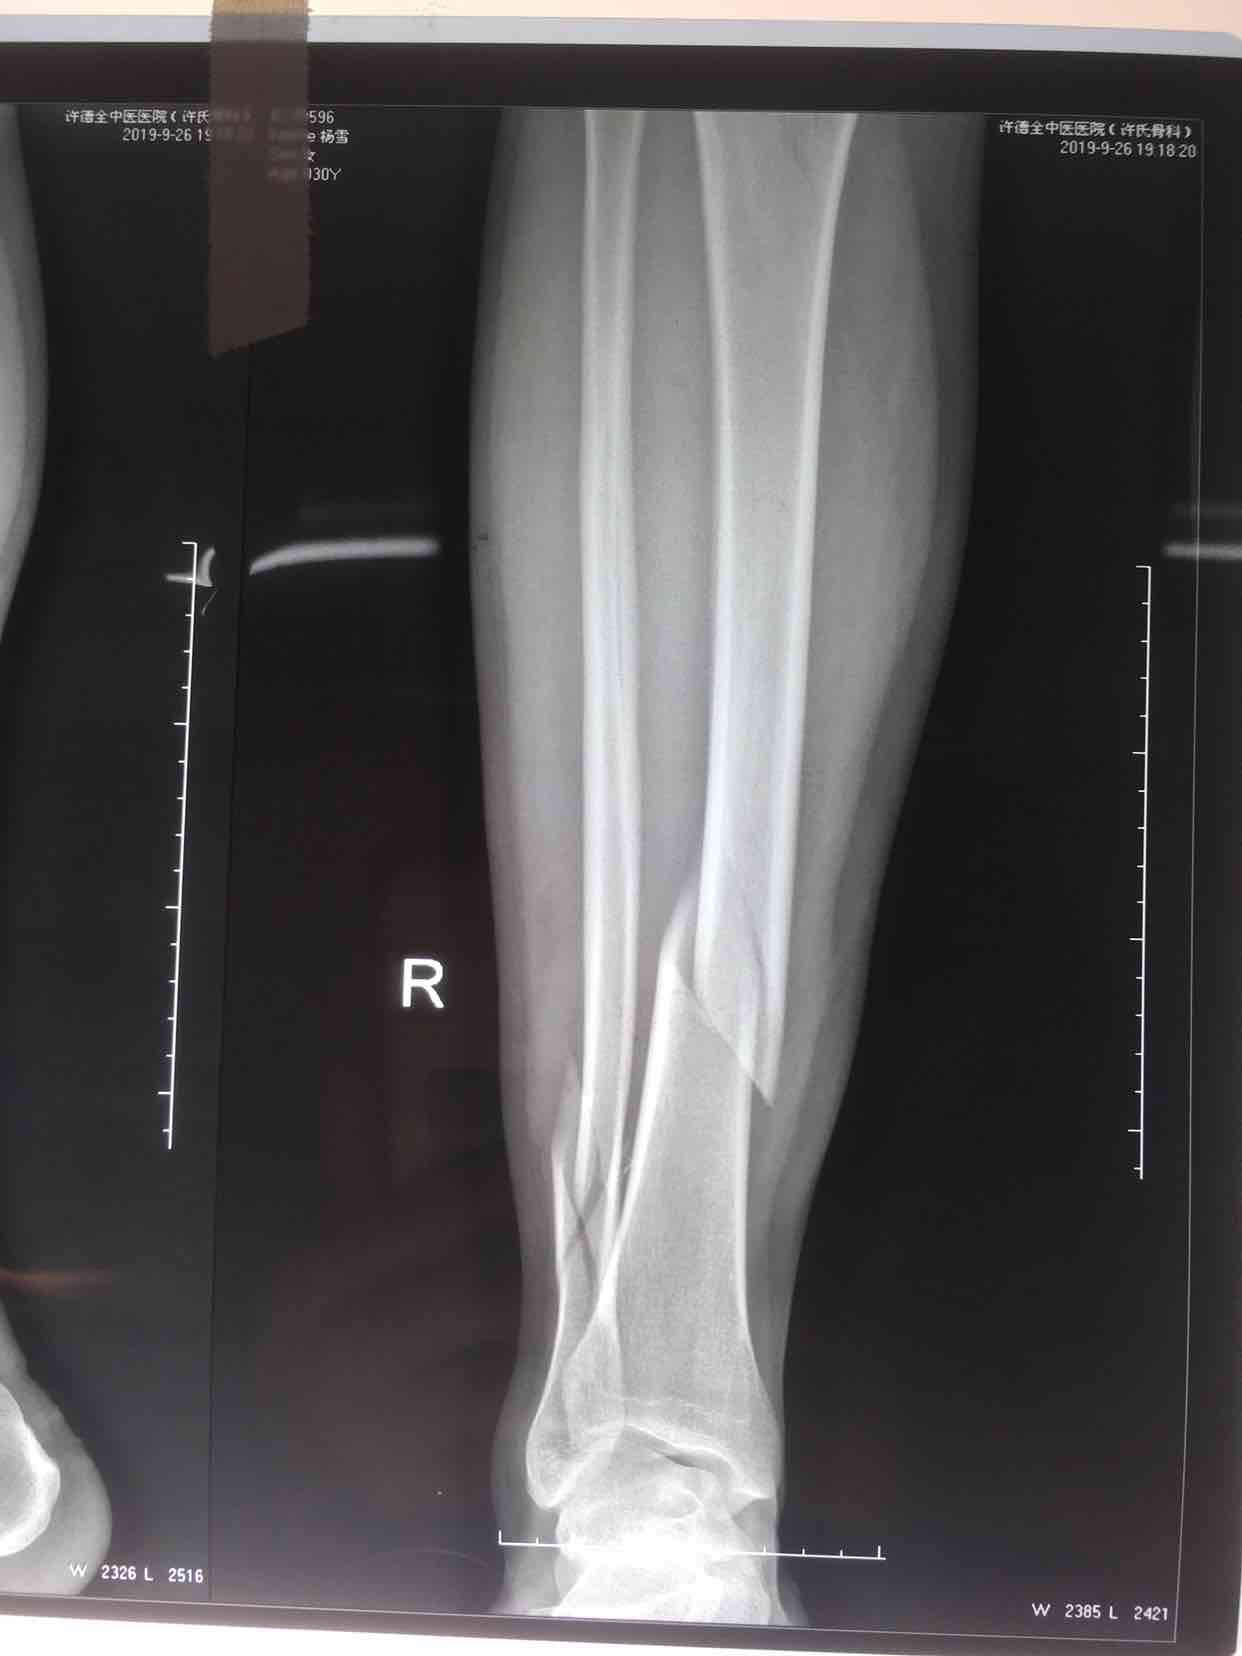

摔伤后右小腿肿胀,畸形,活动受限1小时入院。

生命体征平稳,心肺复未见异常。右小腿肿胀,畸形,局部皮温高,皮色发红,压痛及纵向叩击痛阳性,可及骨檫音及骨檫感,末梢血运感觉正常。

诊断右胫腓骨粉碎性骨折